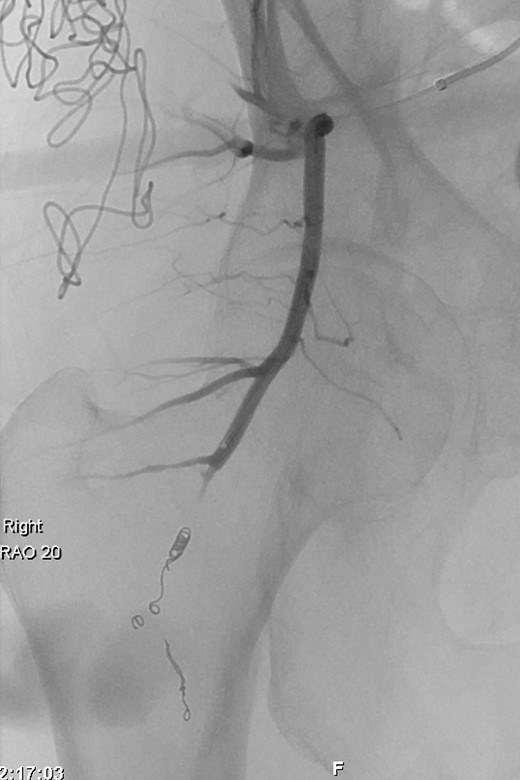

The patient continued to be haemodynamically stable throughout Thursday (day 7), abdomen and pelvis contrast CT indicated two bleeding sites arising from the internal iliac artery region. One was identified arising from the posterior division of the right internal iliac artery, at the inferior gluteal artery (Fig. 1a). A second, less prominent bleeding point was noted at the division level of the internal iliac artery into its anterior and posterior branches, anterior to the sacroiliac joint (Fig. 1b). Selective angiography was also performed, identifying a large pseudoaneurysm arising from the inferior gluteal artery and endovascular repair was undertaken (Fig. 2). The right common iliac artery was accessed via a left common femoral artery puncture and a combination of five 2 × 5.0 mm Figure 8–18 pushable coils and two VortX™-18 pushable coils of 3 × 2.5 mm and 4 × 4.0 mm respectively (Boston Scientific, Massachusetts, USA) were deployed to embolize the inflow and outflow vessels (Fig. 2). A further 200 mls of blood were evacuated from the right buttock wound post-embolization. Haemostasis was achieved successfully and wound closure undertaken on the following Monday (day 11).

Interventional Angiogram: Deployment of seven coils to embolize the inflow and outflow vessels of the inferior gluteal artery pseudoaneurysm.